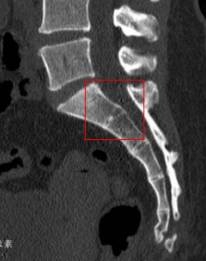

患者CT

2017年7月3日,患者经多方打听,转至我院骨伤一科进行诊治。患者入院完善相关检查,其中骨盆CT显示:骶1骨折(粉碎性骨折),继发相应椎管重度狭窄。再结合患者病史症状体征及其他影像学资料,最后诊断为:不稳定型骶骨骨折。